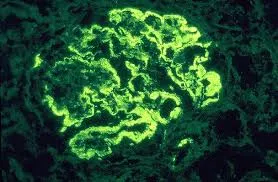

Este vídeo apresenta, de forma didática e baseada em evidências, os principais achados da tese de doutorado sobre amiloidose renal, com foco em proteômica glomerular e ativação do complemento. São discutidos aspectos diagnósticos, implicações fisiopatológicas e correlações clínico-patológicas relevantes para a prática do nefrologista. O conteúdo sintetiza dados inéditos de matriz extracelular glomerular e diferencia perfis entre subtipos de amiloidose. Trata-se de um material aprofundado e acessível, ideal para atualização de especialistas na área.